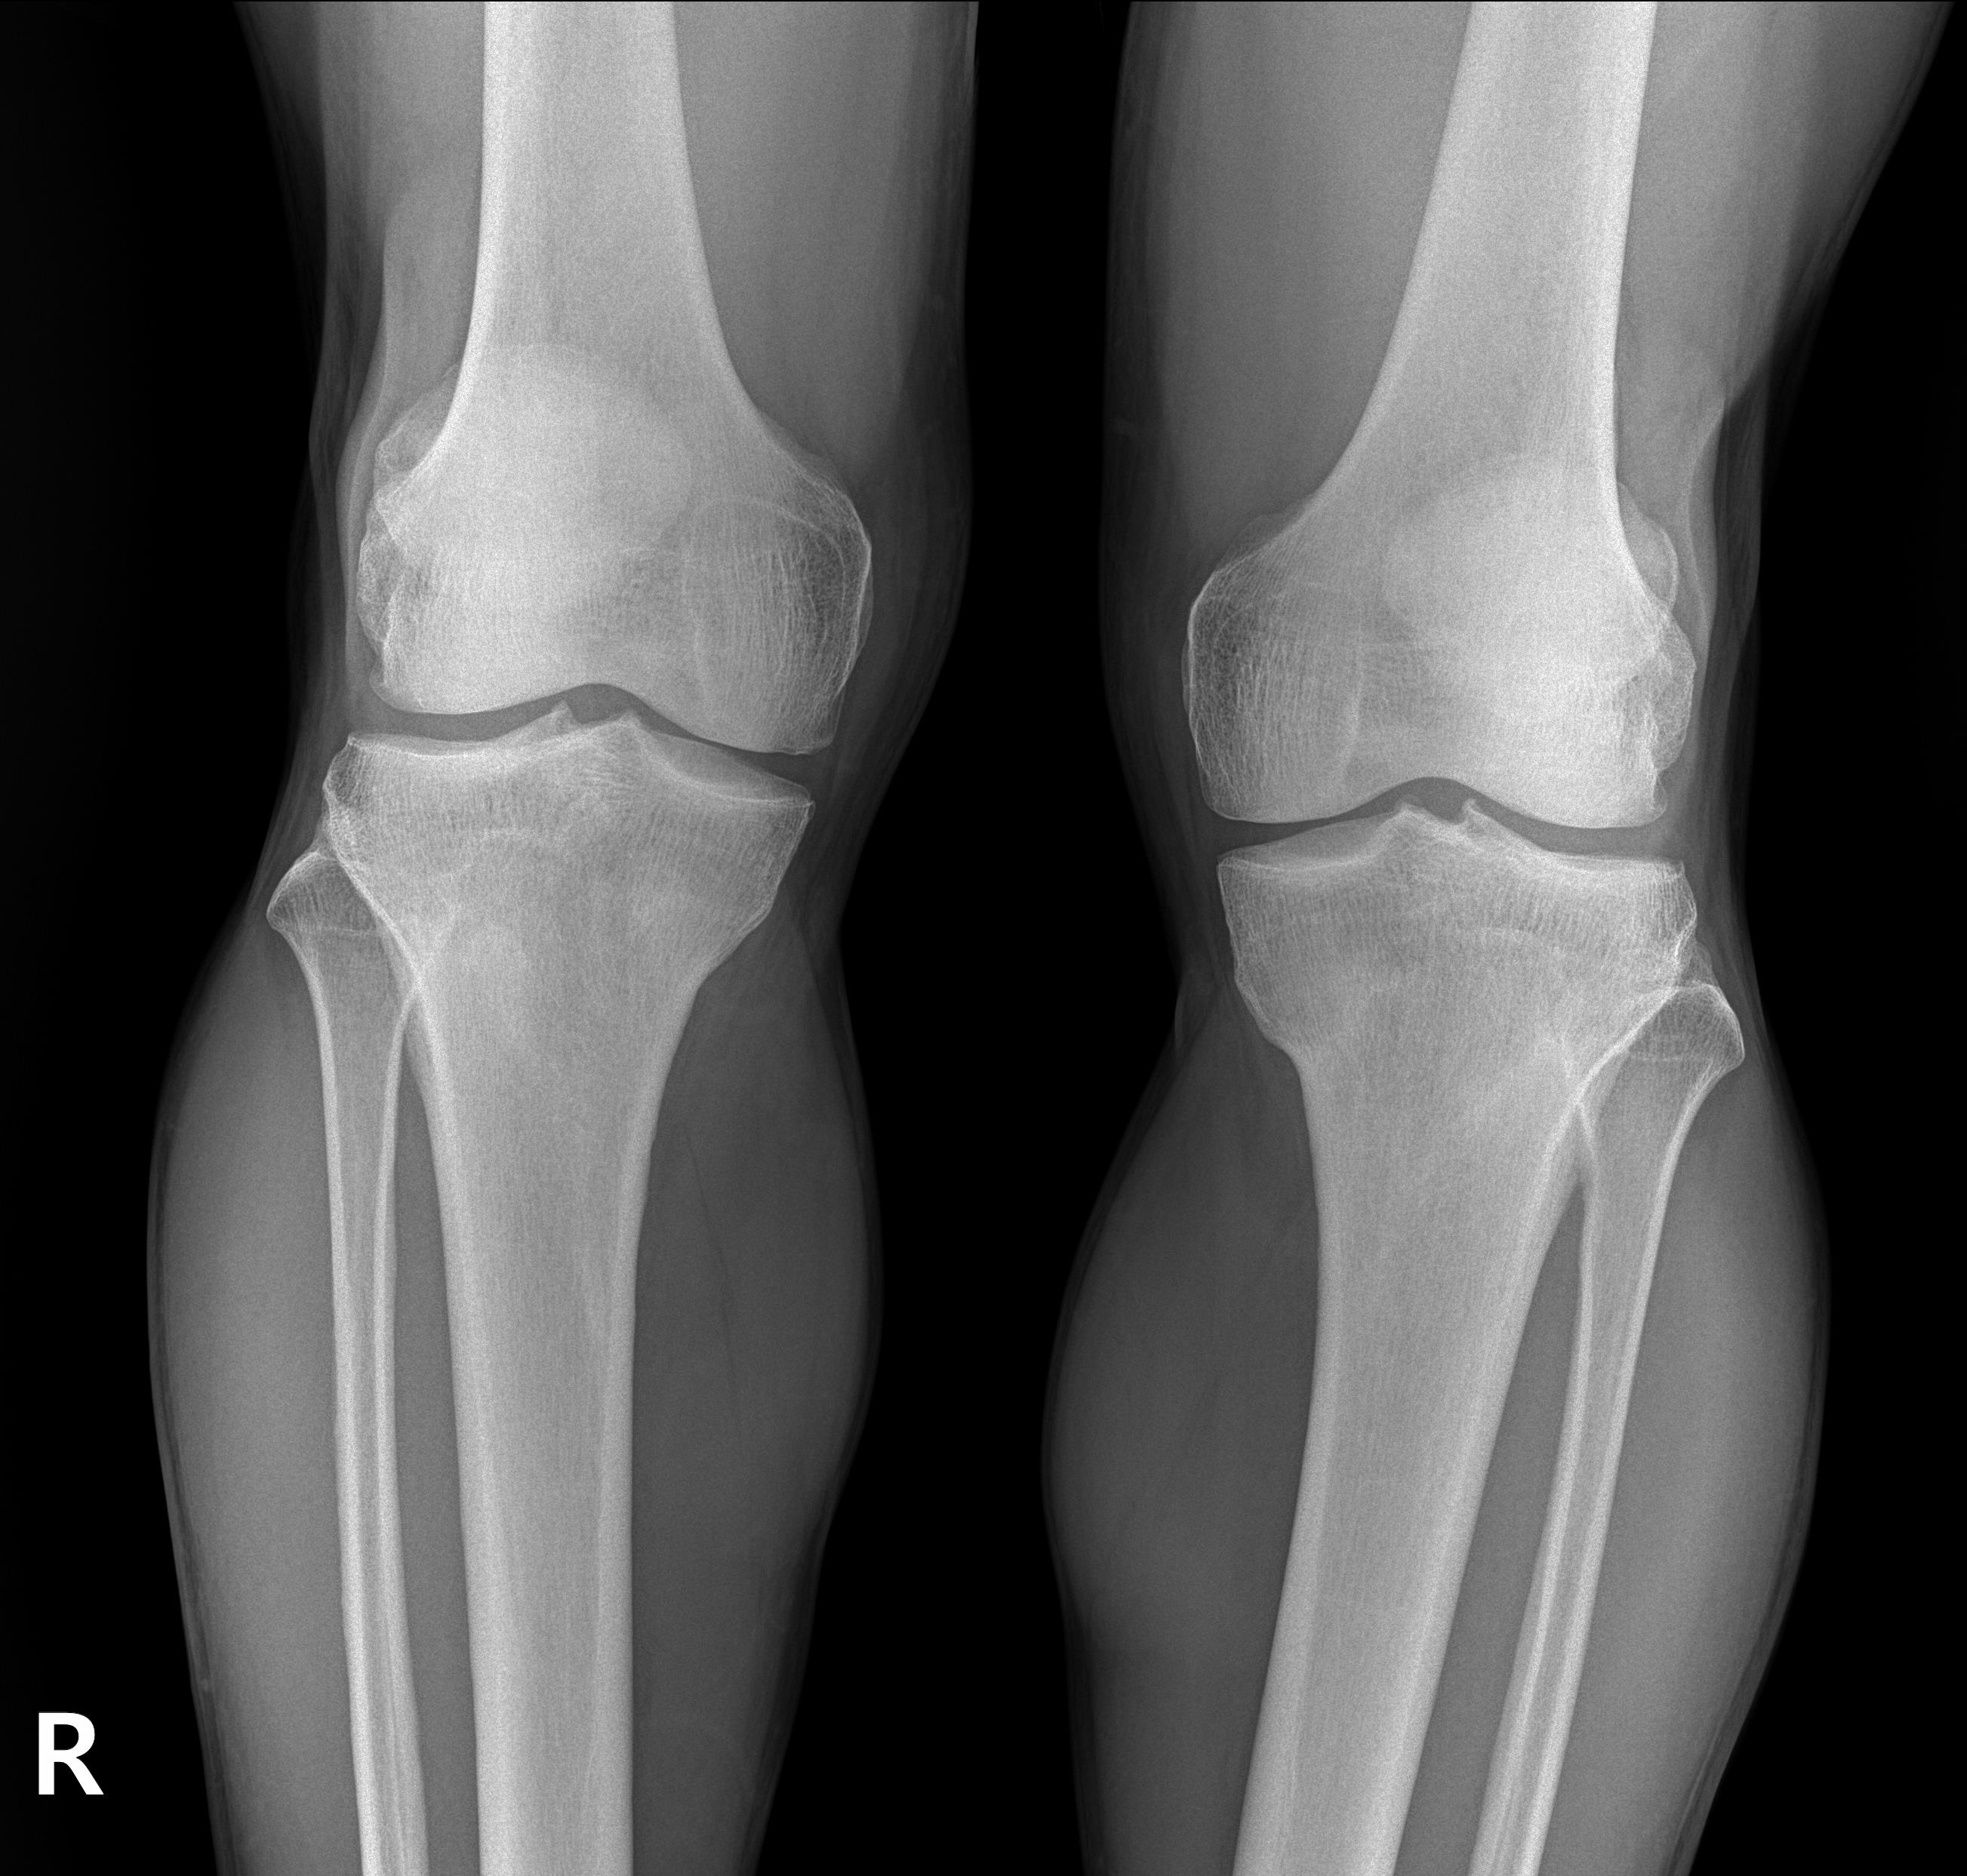

우선 가장 기본적은 X-ray 촬영을 했습니다. X-ray상에서는 퇴행성 초기 소견을 보이기는 하지만 큰문제는 없어 보였습니다.